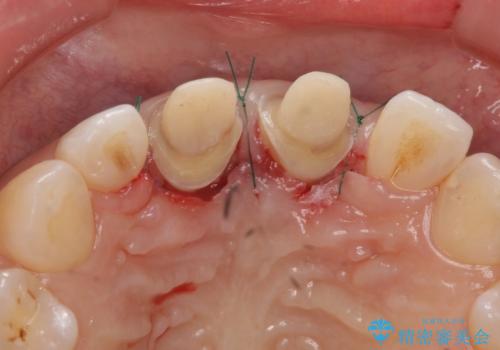

セラミックにする際に神経をとり、無理やり歯の頭の部分のみ内側に引っ込めてありました。

その後、マージンが舌側が深い状態だったため、歯ぐきの手術(歯周外科処置:APF)を行ってから最終的なセラミックを装着しました。

治療途中